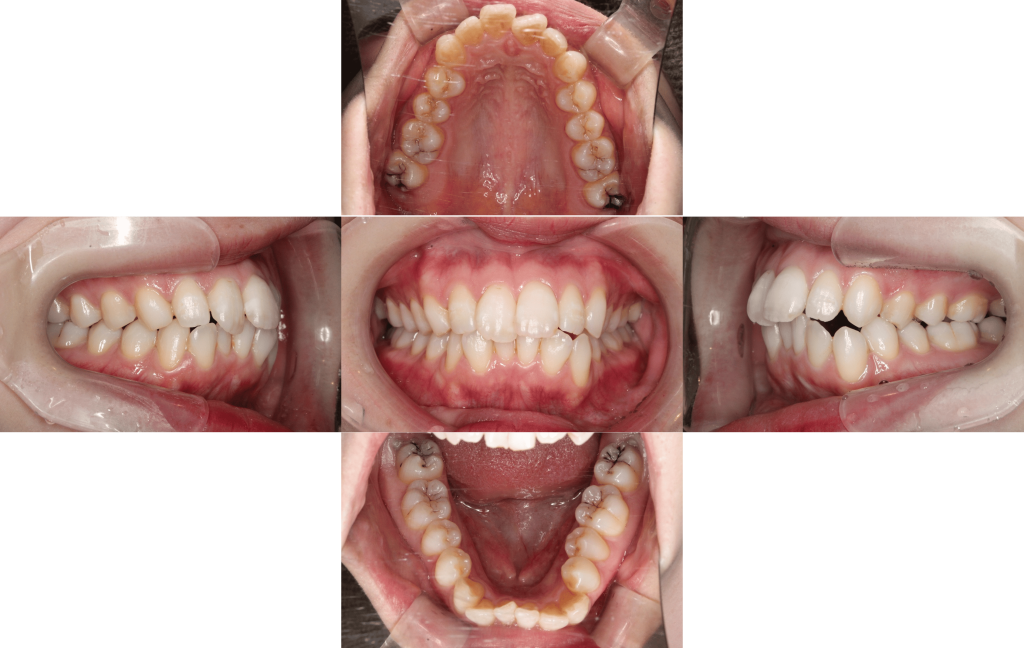

Before

初診